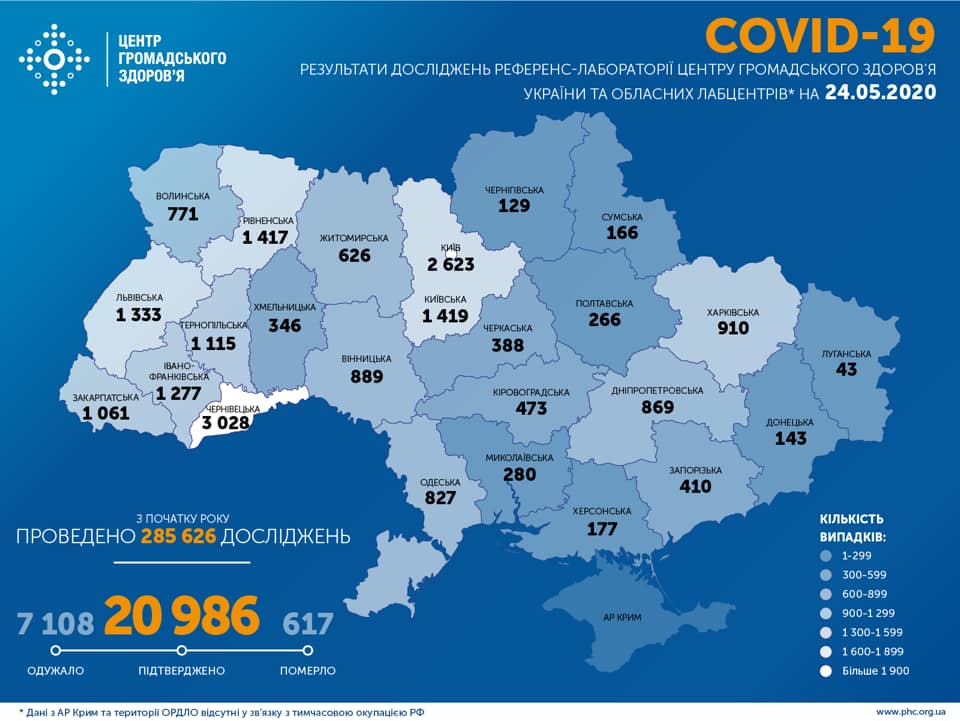

Більше 3 тисяч випадків захворювання на коронавірус зафіксували в Україні за добу

11.09.2020 09:37

COVID-19 на Рівненщині: 32 нових випадки, серед них 4 дітей, ще одна людина померла

22.05.2020 19:19